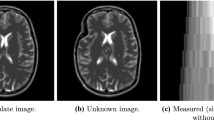

A new approach to maximum entropy tomographic image reconstruction is presented. It is shown that by using a finite-dimensional subspace, one can obtain an approximation to the solution of a maximum entropy optimization problem, set inL 2 D. An example of an appropriate finite element subspace for a two-dimensional parallel beam projection geometry is examined. Particular attention is paid to the case where the x-ray projection data are sparse. In the current work, this means that the number of projections is small (in practice, perhaps only 5–20). A priori information in the form of known maximum and minimum densities of the materials being scanned is built into the model. A penalty function, added to the entropy term, is used to control the residual error in meeting the projection measurements. The power of the technique is illustrated by a sparse data reconstruction and the resulting image is compared to those obtained by a conventional method.